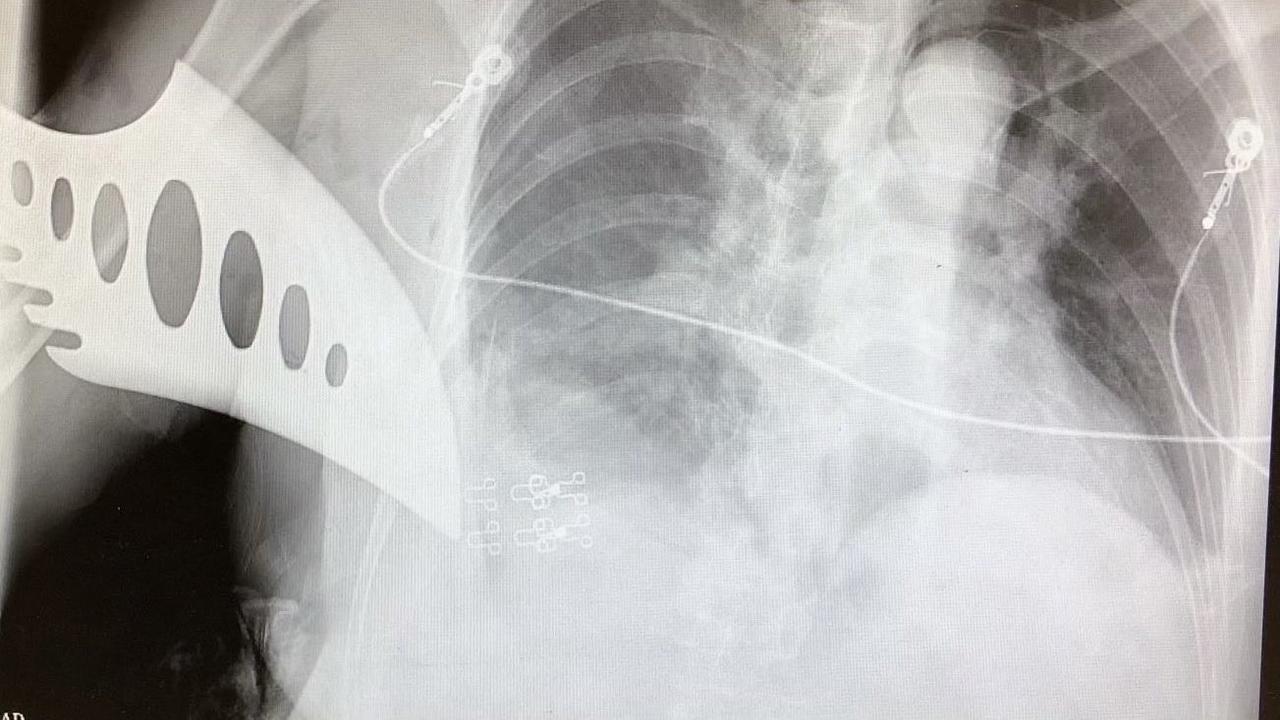

Pisaunya patah saat menusuk korban yang berusia 85 tahun, yakni Chui Fong. Kedua korban selamat dan sedang dirawat di rumah sakit.